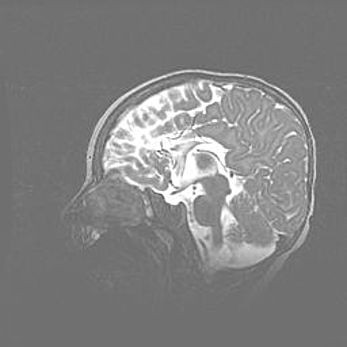

Лейкомаляция с кистозно-глиозной дегенерацией головного мозга.

Возраст: 2 месяца 25 дней

Вес: 6400 г

Окружность головы: 40 см

Срок гестации: 41 неделя

Лейкомаляцию относят к ишемически-гипоксическим повреждениям головного мозга, диагностируемым у новорожденных. При лейкомаляции в головном мозге обнаруживают очаги некроза, возникшие после тяжелой гипоксии и нарушения кровотока. В процессе морфогенеза очаги проходят три стадии: 1) развития некроза, 2) резорбции и 3) формирования глиозного рубца или кисты. Перивентрикулярная лейкомаляция (ПЛ) встречается примерно в 12% случаев среди новорожденных, обычно – у недоношенных детей, причем, частота ее зависит от массы, с которой младенец появился на свет. Наибольшее число малышей страдает лейкомаляцией, если масса при рождении 1500-2500 г.